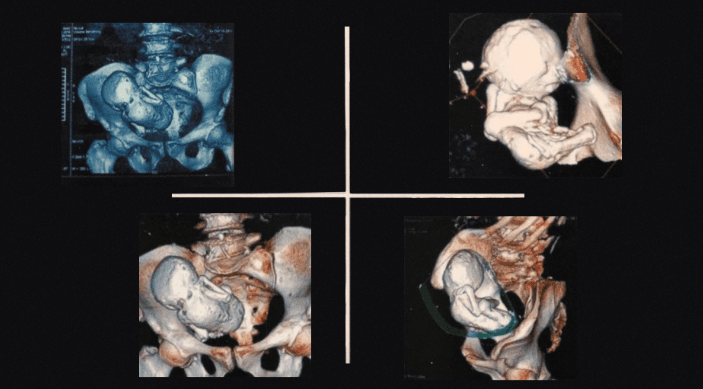

Как пишет N+1, сначала женщине назначили терапию от инфекции мочевыводящих путей, однако через несколько дней ей провели компьютерную томографию с 3D-моделированием, которая показала кальцифицированный плод в брюшной полости.